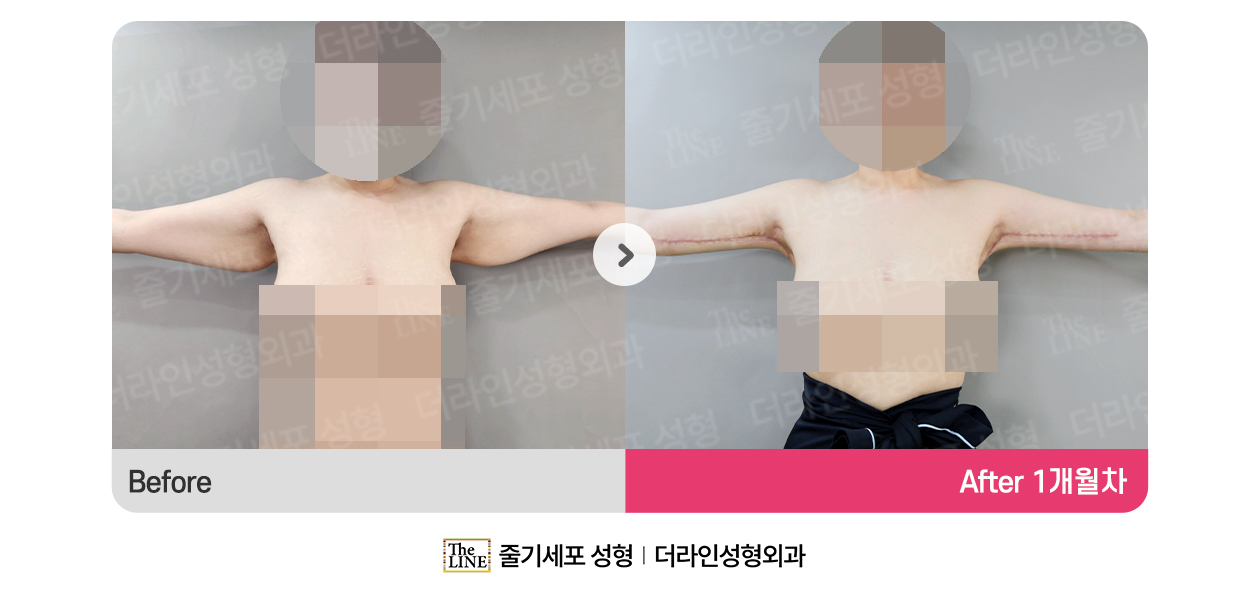

Before & After

การยกกระชับต้นแขนที่ The LINE

อาจเกิดผลข้างเคียงที่ไม่คาดคิด เช่น การอักเสบ เลือดออก หรือการติดเชื้อ

ความรุนแรงของอาการอาจแตกต่างกันไปตามแต่ละบุคคล กรุณาระมัดระวัง